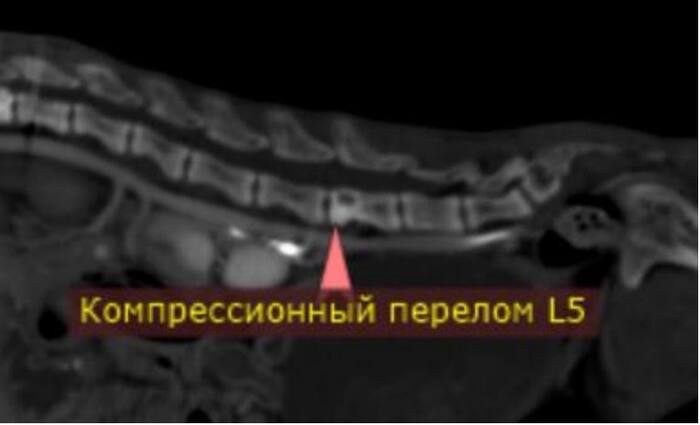

Я иногда пишу про компьютерную томографию животным, но сфера узкая и находит мало откликов в сердцах коллег. Хотя по-моему это фантастически интересно и очень красиво. Наткнулась на пост с интересными рентгеновскими снимками и подумала, а вдруг, вдруг кому-то и мои снимочки будут интересны?

К делу:

Болезнь собаки мясника - околонародное название для алиментарного гиперпаратиреоза (вторичного пищевого гиперпаратиреоза) Заболевание связано с вымыванием кальция из костей и органов из-за нарушения соотношения количества кальция и фосфора в крови и развивается при несбалансированном кормлении животных (как правило, при кормлении одним мясом: поэтому и «болезнь собаки мясника». Мяснику очень удобно кормить сабачку обрезью и прочим, а потом не затруднительно заменить на новую собаку) (это я не обижаю никак мясников, это я поясняю смысл термина).

Так вот, недостача кальция в пище приводит к тому, что организм начинает компенсировать её своими силами, и начинает вымывать кальций из мест депонирования в организьме. Из кишечника, других органов, из костей.

Это в свою очередь приводит к тому, что кости становятся визуально полупрозрачными, физически непрочными и ломкими. Такие зверята начинают случайно ломаться в разных местах, деформироваться и страдать от боли. На приёме как правило оказывается неходячее и очень болящее животное.

Возможности вылечить зависят от того, где, сколько раз и насколько неудачно пациент сломался. И от возможности донести до владельцев необходимость сбалансированного питания.

Немножко сканов котенка, которого кормили мясом. Кости становятся хрупкими и могут буквально складываться, как бумага (особенно позвонки и кости лап. Часто такие животные, если их удается полечить, имеют аномально изогнутый позвоночник и кривые другие кости):